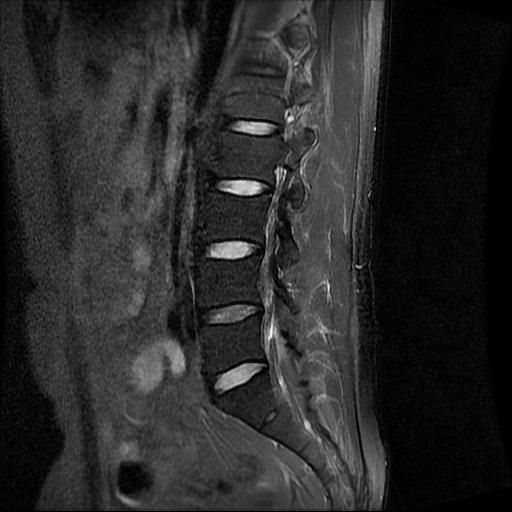

허리 MRI 전문가분들 의견부탁드립니다.

이번에 허리 MRI찍었는데

상태 어떤지 고견 여쭙습니다.

• 1번 째 사진

큰 이상이나 문제점은 없어 보이는 것으로 생각되는데요, 허리통증이 지속되는 경우에는 반드시 디스크 질환에 의한것은 아닐 수 있습니다.

현재로썬 디스크 상태는 심하지않는것으로 확인이 됩니다.